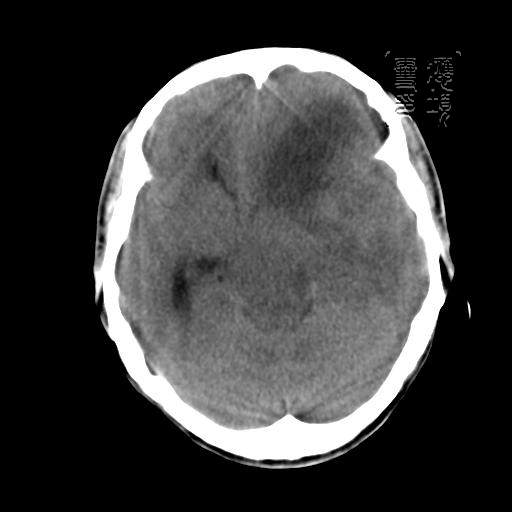

m 52y

二月前癫痫入院, 无既往史,现头痛、呕吐、视力减退、复视行ct平扫及增强检查。

见环形,结节样强化,考虑囊性星型细胞瘤。

考虑囊性星型细胞瘤,ct征象大囊小结节.

左额叶囊实性占位,以囊性为主,并见明显强化不规则壁结节,占位效应明显,首先考虑是囊性星形细胞瘤.

从发病部位及年龄都不考虑是血管母细胞瘤,还有可能是胶质瘤.